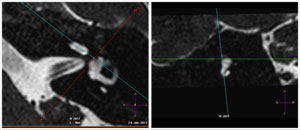

MRI imaging of the inner ear